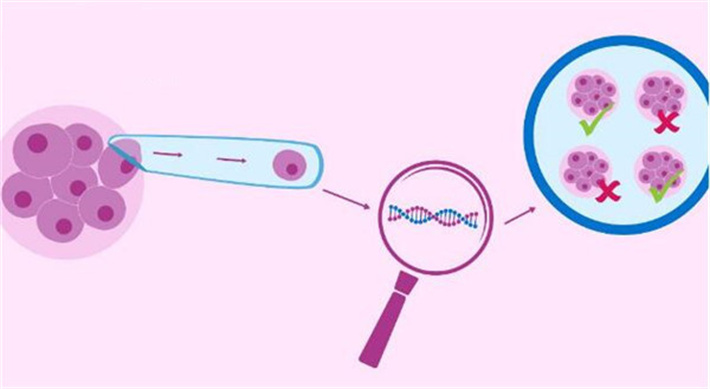

美国第三代试管婴儿即PGD/PGS基因检测技术,是指在胚胎移植前,提取胚胎的遗传物质进行分析,诊断是否存在异常,筛选健康胚胎进行移植,防止遗传病传递的方法。

赴美做试管,HRC专家会提取囊胚的4到8个外围细胞,用聚合酶链反应(PCR)、萤光原位杂交(FISH)等检测囊胚是否存在遗传病、染色体病等。

5、基因检测

养囊成功后,HRC专家会运用先进的第三代试管婴儿技术对囊胚进行基因检测,筛查囊胚染色体是否存在缺失、倒置、易位等异常情况,诊断其是否携带遗传缺陷基因或导致某种疾病的基因突变,从而筛选出健康的囊胚用以移植。